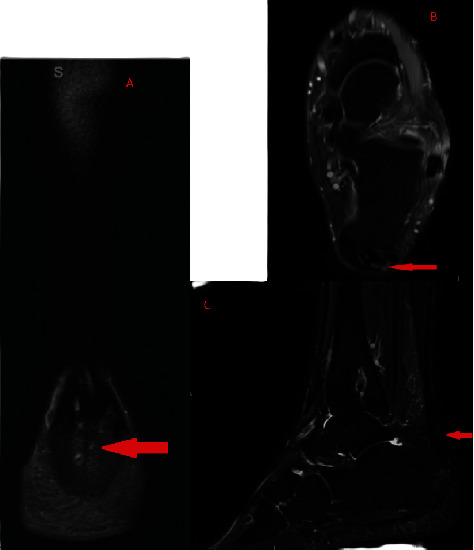

跟腱修复术后数年,之前的手术部位周围形成痛风性结石是一种极为罕见的病症,文献中仅记载过三例。在本病例中,我们报告了一名 53 岁男性的病例,他在两年半前进行过跟腱修复手术,并且没有痛风的临床病史,但在对跟腱进行必要的翻修手术时,我们发现他在初次手术修复时使用的不可吸收缝线周围出现了痛风性结石。这个病例和之前的三个病例都涉及到不可吸收缝合线的使用,这些缝合线有可能成为手术多年后痛风性跟腱炎形成的巢穴,即使是没有痛风临床病史的患者也可能出现痛风性跟腱炎。临床医生必须注意这种罕见的临床表现,因为潜在的后遗症包括感染过程和需要进行翻修手术。

The formation of gouty tophi surrounding the prior surgical site years after an Achilles tendon repair is an extremely rare presentation for which only three previous cases have been documented in the literature. In this case, we report the presentation of a 53-year-old male who had an Achilles tendon repair two and a half years prior and no clinical history of gout, yet during the necessary revision procedure of his Achilles tendon, he was found to have gouty tophi surrounding the nonabsorbable sutures used during his initial surgical repair. This case presentation and the three prior ones all involve the use of nonabsorbable sutures, and these sutures may potentially serve as a nidus for the formation of gouty tophi years after a surgical procedure, even in patients who do not have a clinical history of gout. It is important for clinicians to be aware of this rare clinical presentation as potential sequelae include infectious processes and the need for revision procedures.